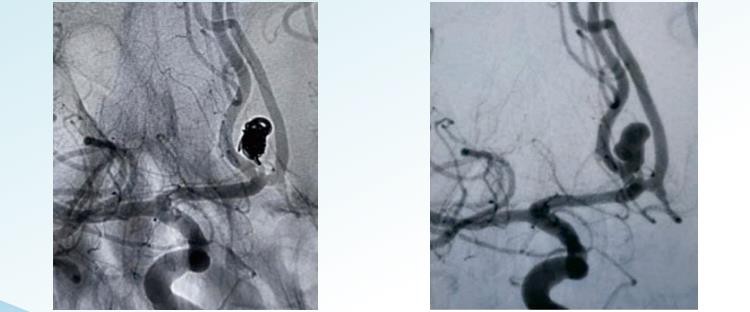

RenovierungTMDas abnehmbare Aneurysma-Coiling-System bietet zufällige, spiralförmige und abnehmbare 3D-Optionen für die endovaskuläre Embolisation in Durchmessern von 1 bis 22 m. Es ist für die Embolisierung von Aneurysmen vom Rahmen bis zum Ende konzipiert und umfasst Spulen, die speziell für eine konzentrische Aneurysmafüllung geformt sind, sowie Spulen mit großem Volumen, um eine hohe Packungsdichte zu erreichen. Random Coiling ist die einfachste und älteste Form der Aneurysma-Coiling-Technik. Dabei wird eine einzelne Spule oder eine Gruppe von Spulen in das Aneurysma eingeführt. Die Spulen bestehen normalerweise aus Platin und sind dünn und eng gewickelt, um die Bildung von Lücken oder Hohlräumen im Beutel zu verhindern. Beim spiralförmigen Wickeln wird ein längerer, dünner Draht verwendet, der spiralförmig um sich selbst gewickelt ist und so eine federartige Struktur bildet. Der Draht wird in gestreckter Form in das Aneurysma eingeführt. Sobald er sich im Inneren befindet, kann er sich aufrollen und ausdehnen, um den Aneurysmasack zu füllen. Helikale Spiralen sind breiter und dichter gepackt als zufällige Spiralen und sorgen so für einen besseren Verschluss des Aneurysmas. Bei der 3D-Spule kommt eine speziell angefertigte Spule zum Einsatz, die mithilfe eines computergestützten Bildgebungsverfahrens hergestellt wird und ein exaktes dreidimensionales Modell des Aneurysmas erstellt. Die Spule wird exakt an die Größe und Form des Aneurysmas angepasst. Dieser Spulentyp ist so konzipiert, dass er genau in den Aneurysmasack passt, eine hervorragende Okklusion bietet und das Risiko von Komplikationen verringert. 3D-Spulen sind besonders wirksam bei der Behandlung schwer zugänglicher Aneurysmen oder in fragilen Blutgefäßen.

RenovierungTMAbnehmbare 3D-Spulen

RenovierungTMSpiralförmige abnehmbare Spulen